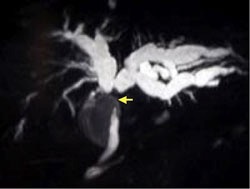

MRCP picture showing swollen right and left hepatic ducts, with a tumour causing a blockage at the confluenceMRI (Magnetic resonance imaging) is another useful scan that yields information similar to CT, but also gives three-dimensional reconstruction of the bile ducts (called MRCP). This can provide a roadmap for the biliary anatomy above and below the tumour.